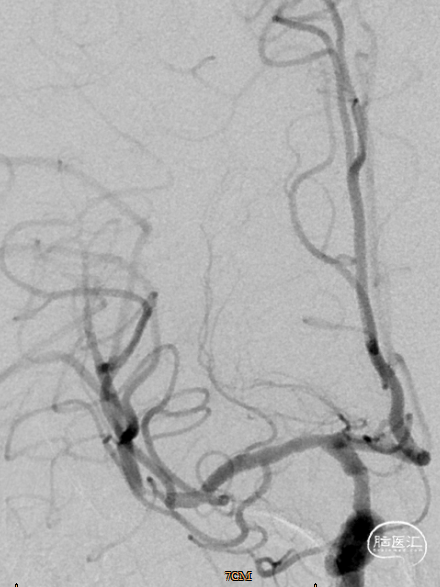

术前影像资料